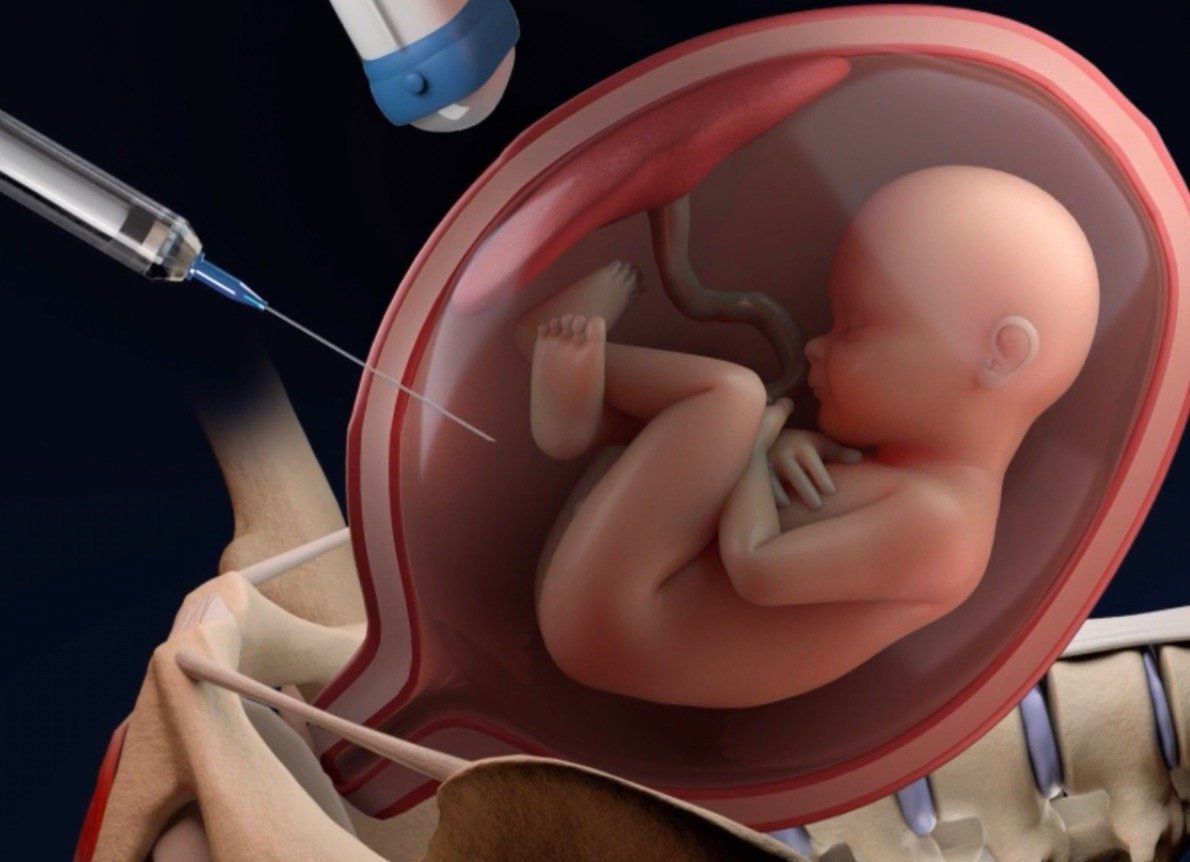

- Trasfusiones intrauterinas

- Cordocentesis

- Amniocentesis

- Biopsia de Vellosidades Coriales